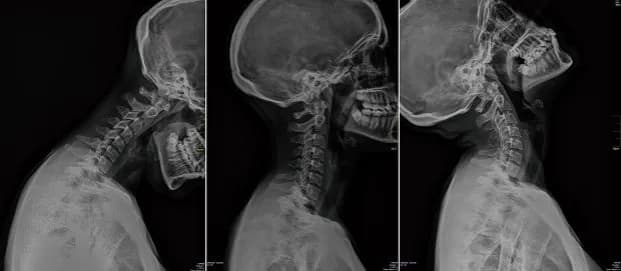

Skręcenie kręgosłupa szyjnego – ile zwolnienia i co warto wiedzieć